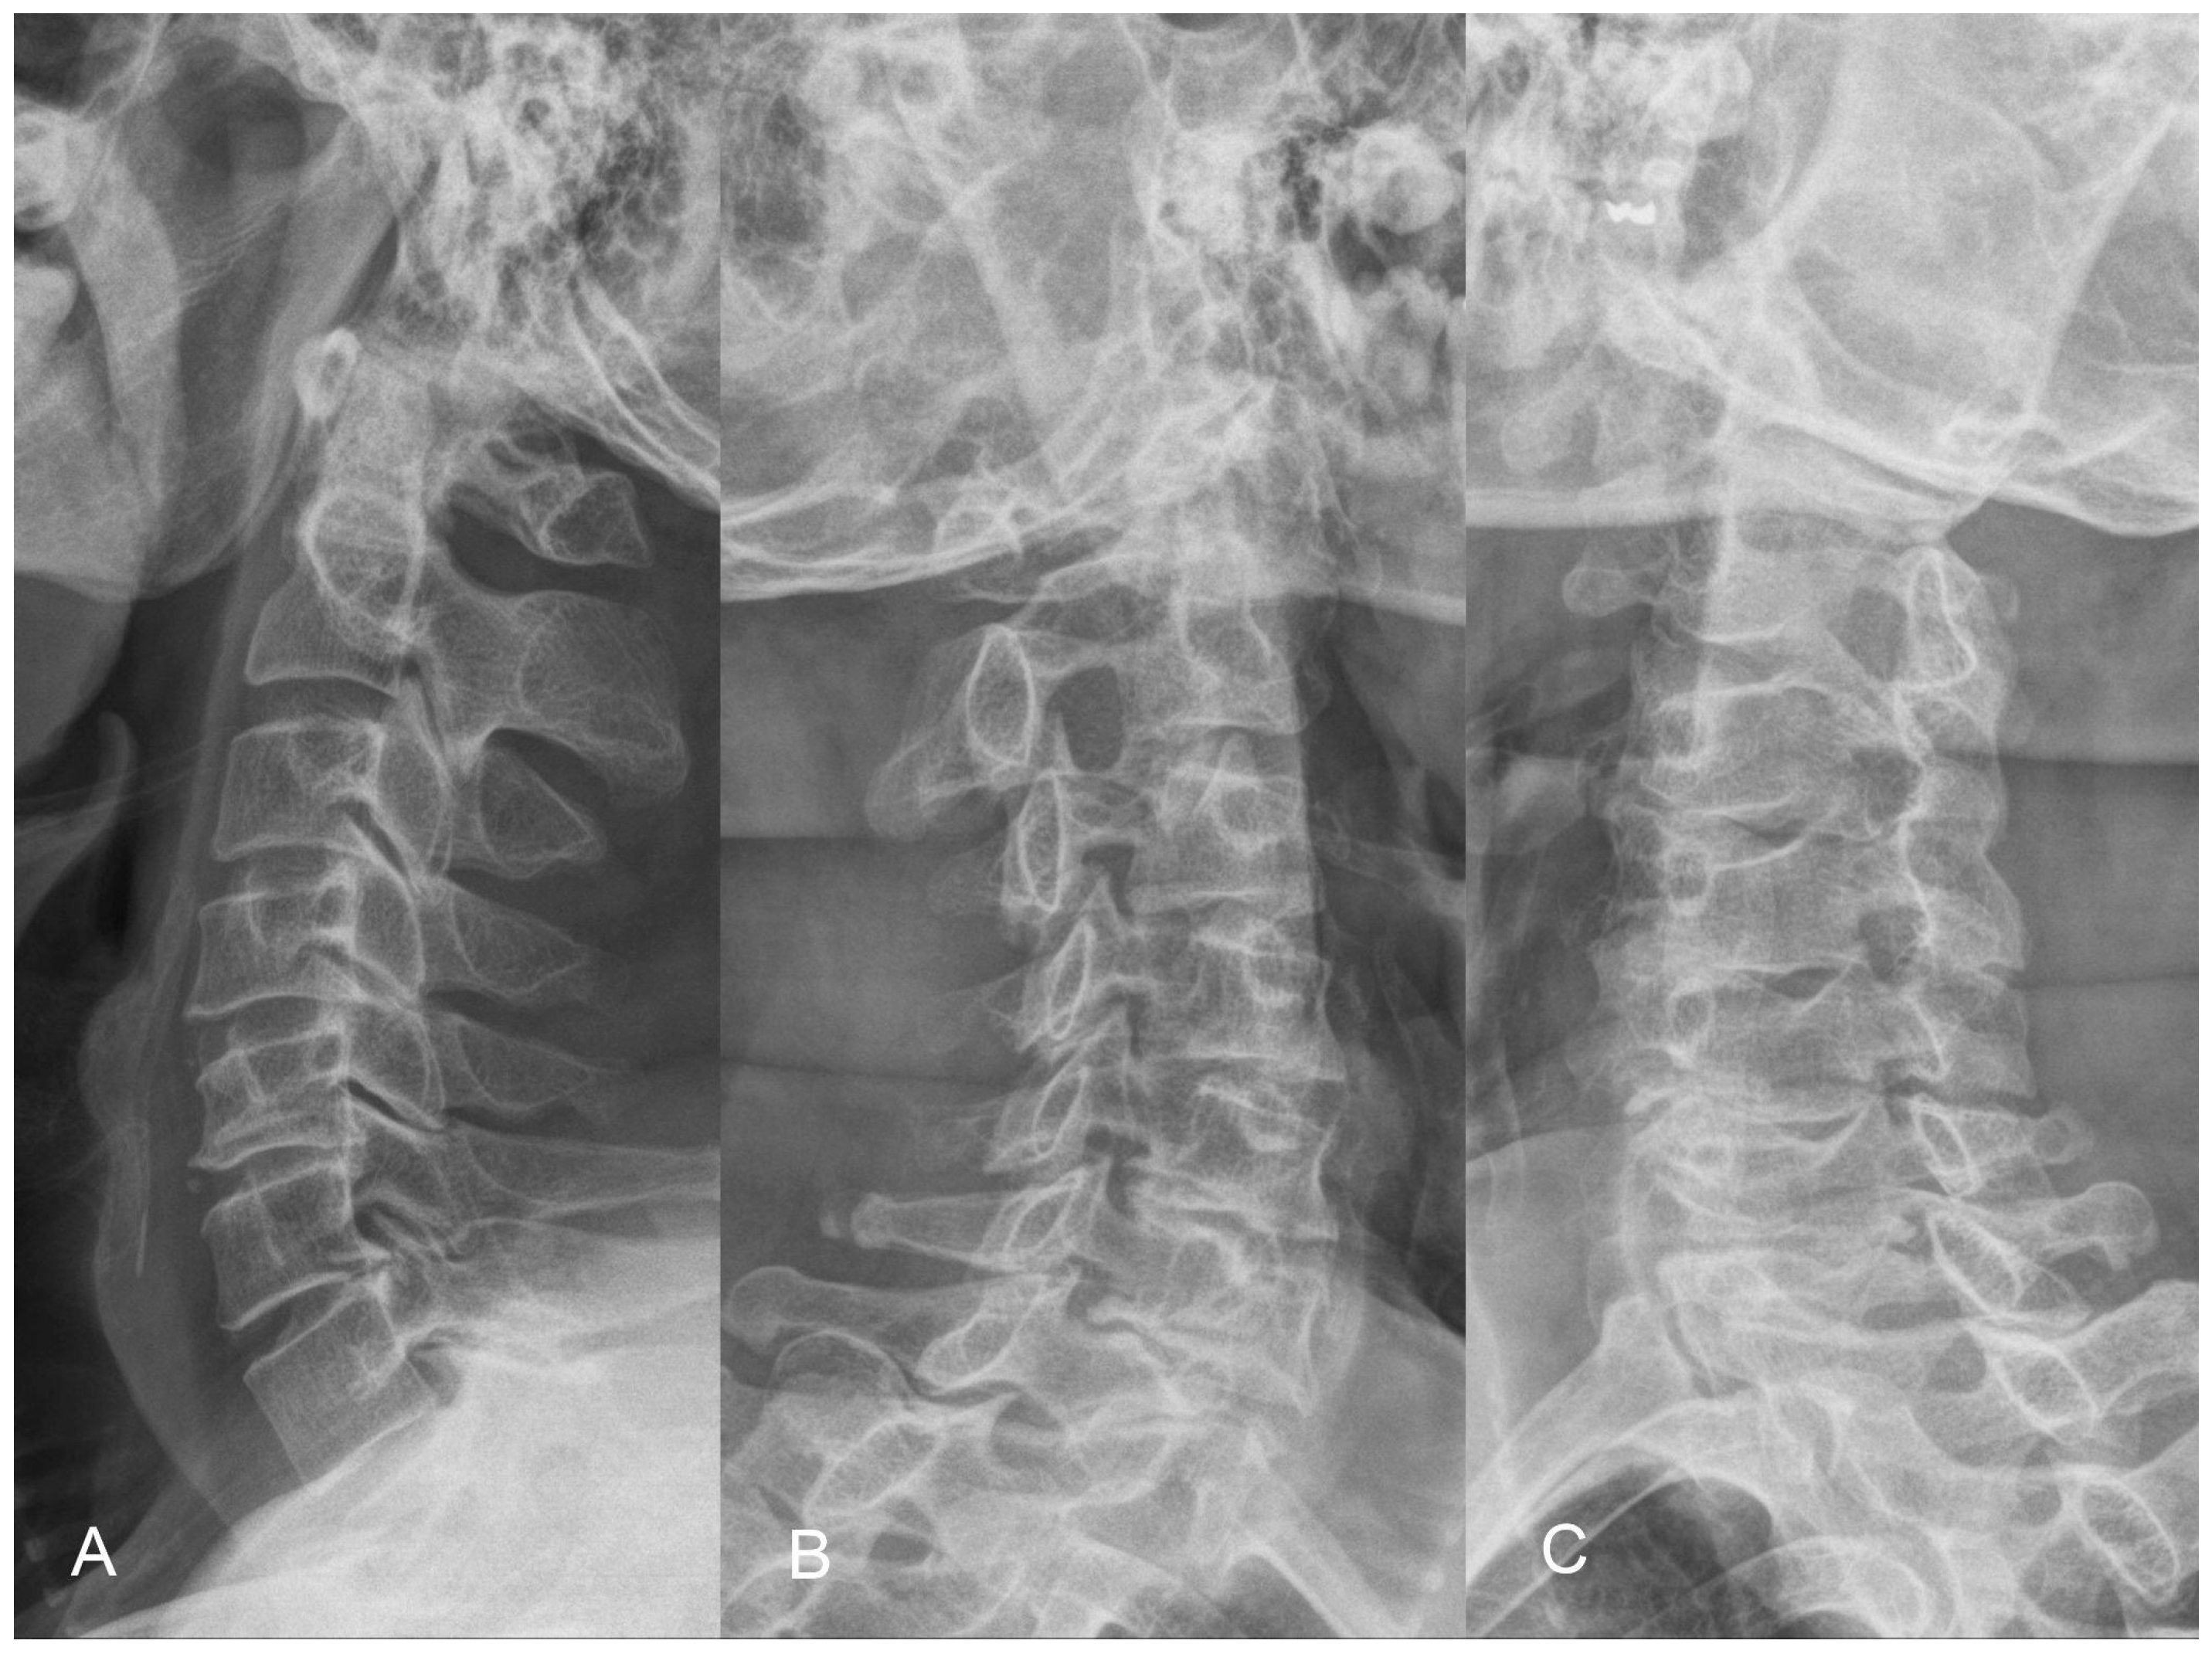

The X-ray demonstrates normal cervical lordosis and a positive K-line. There is evidence of bilateral foraminal spur formation at C3-6 and left foraminal spur formation at C6-7. MRI findings indicate C3-7 degenerative spondylosis with central spinal stenosis at C3-6, bilateral foraminal spur formation with stenosis at C3-6, more pronounced on the right side, and left foraminal spur formation with stenosis at C6-7. However, due to the relatively inconspicuous nature of left-sided radiculopathy, surgical intervention at the C6-7 segment was not pursued (Figure 8 and Figure 9). The patient’s preoperative modified Japanese Orthopaedic Association score was recorded as 16, and his visual analog scale neck pain was rated at 8.

Figure 8. Preoperative lateral (A) and oblique radiographs (B,C) demonstrating well-maintained sagittal lordosis alignment and C3 to C7 foraminal stenosis, accompanied by the formation of osteophytes.